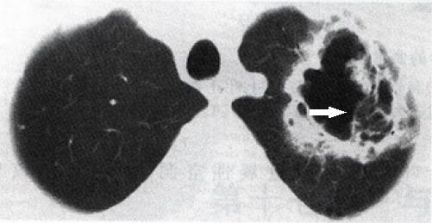

例3:患者患有慢性阻塞性肺疾病(慢阻肺病)营养不良,院外不规则口服激素,反复咳嗽,咯血

图5 胸部CT

图5 胸部CT这个空洞乱糟糟的,要考虑鳞癌。但是,患者免疫力低下,空洞里面有网状影,考虑是增生的真菌。有时候肺结核空洞也会这样,但是结核干酪性坏死,里面会死的很彻底,一般是空荡荡的。这种蜘蛛网,曲霉菌病可能性。

结合病史、CT,诊断:慢性坏死性曲霉菌病。